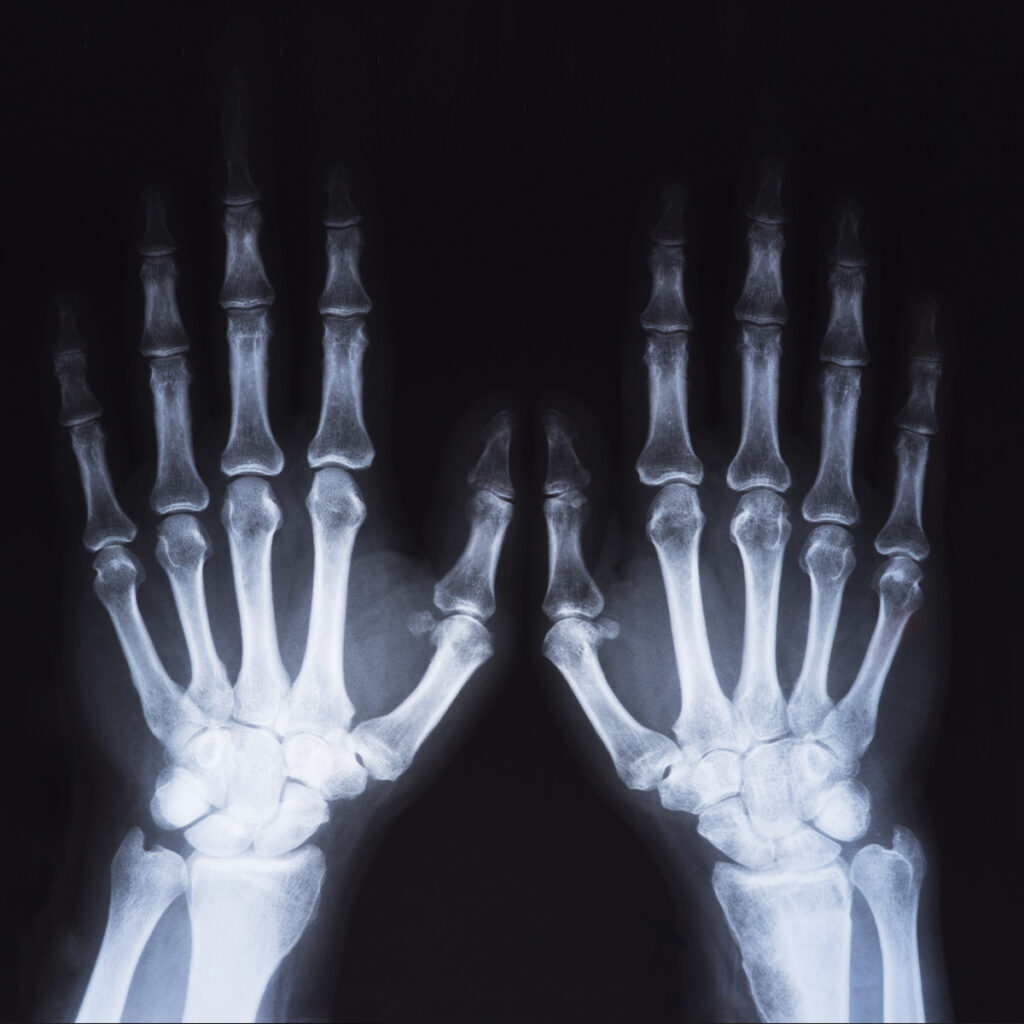

RADIOGRAFIA DELLE ARTICOLAZIONI E DELLE OSSA

Trova il suo utilizzo nello studio dell’osso e delle articolazioni in seguito a traumi, artropatie come l’artrosi e dolori articolari.